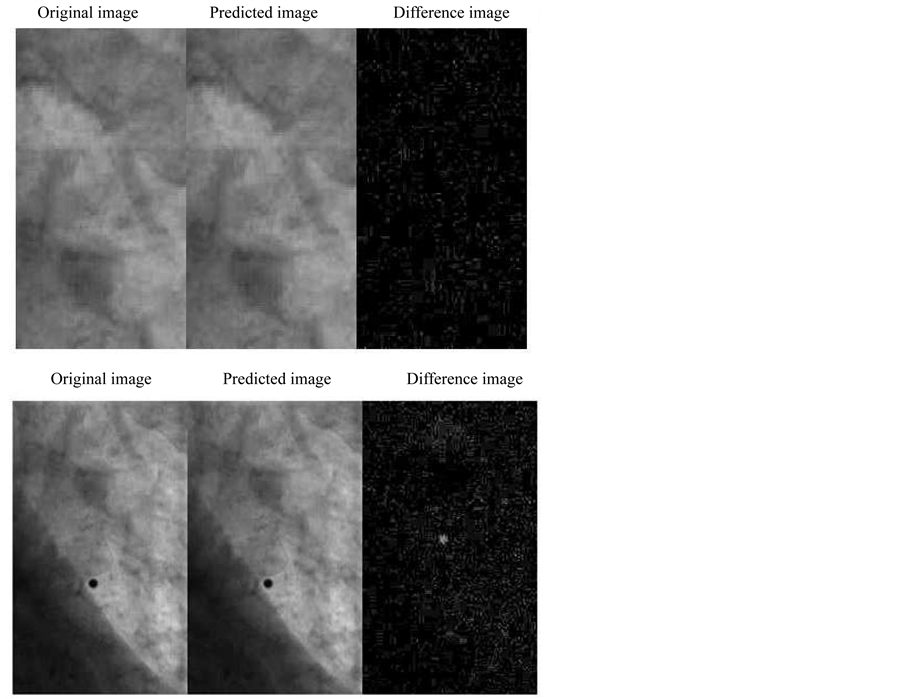

In contrast to 4DCT images, first twenty principal components had to be collected for the precise image prediction in kV fluoroscopic images. Figure 7 shows the prediction result for the kV fluoroscopic images including the tumor and tumor with marker, respectively. The quantitave anlaysis of the prediction result using cross correlation gave 0.9984 ± 0.0017 and 0.9957 ± 0.0030 with and without marker, respectively (Table 1).

Figure 7. Tumor only prediction (upper) and with marker prediction (bottom) for the kV fluoroscopic images.

Our input kV fluoroscopic images include both tumor and the marker. We have shown the prediction result including the marker (tumor and marker) and without the marker (only tumor). In both cases there is no much change in the correlation coefficient but there is significant reduction in time due to the reduction of the image size (smaller ROI) hence this method eliminates the use of considering markers. It can also be seen from the result in Figure 7 that due to characteristics of PCA the difference image is only the minor components that are not considered in the prediction.